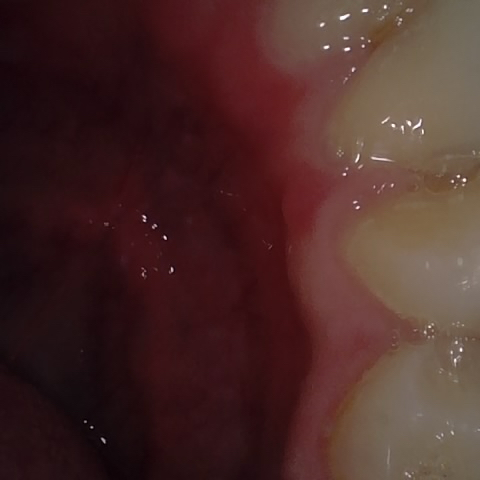

Annotated as "Bad"